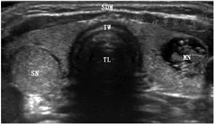

4.超声成像。超声检查用于确定甲状腺的体积和结节的回声、边缘、形状、实质、钙化、血管分布、大小和弹性,此外还有区域淋巴结的状况(图1;补充文件1;补充材料可见于http://jnm.snmjournals.org)。欧洲甲状腺协会[12]、美国放射学会[13]和美国甲状腺协会[14]根据甲状腺影像报告和数据系统(thyroid imaging reporting and data system, TI-RADS),发布了对甲状腺结节恶性风险进行分层的指南(各指南略有不同)。以超声为基础的标准(表1和表2)将甲状腺结节的恶性风险划分为5类,这与之前将超声恶性风险分为3类的共识指南[15]有所不同;使用不同的欧洲甲状腺协会甲状腺影像报告和数据系统(European Thyroid Association thyroid imaging reporting and data system, EU-TIRADS)评分的甲状腺结节例子见补充文件2。仅根据超声标准划分,大约50%的结节可以归类为良性,且低风险结节的假阴性风险仅为0.3%[12]。目前,关于哪个TI-RADS版本能提供更好的结果,仍然存在争议[16,17]。超声引导对于在细针抽吸活组织检查(fineneedle aspiration biopsy, FNAB)[18]和微创治疗过程中[19]的定位至关重要。